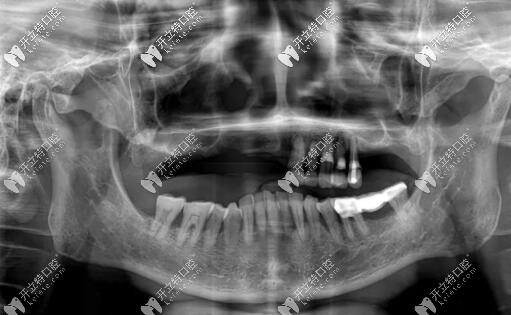

主訴:上頜活動義齒不適,重新修復(fù)。

修復(fù)前

病史上頜于10年前因牙周病導(dǎo)致的牙齒缺失,曾做過可摘戴活動義齒修復(fù)。

經(jīng)過美奧口腔種植牙牙醫(yī)王沖和多個醫(yī)生會診,為惠先生制定了以下種植方案

惠先生種植方案:前期ALL-ON-4即刻負(fù)重,后期上頜竇外提升,同期植入兩顆種植體,做ALL-ON-6,馬龍一體橋。